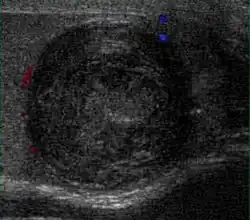

Fibrous pseudotumors, also known as fibromas are thought to be reactive, nonneoplastic lesions. They can occur at any age, about 50% of fibromas are associated with hydrocele, and 30% are associated with a history of trauma or inflammation (Akbar et al., 2003). Although the exact cause of this tumor is not completely understood, it is generally believed that these lesions represent a benign reactive proliferation of inflammatory and fibrous tissue, in response to chronic irritation. Sonographic evaluation generally shows one or more solid nodules arising from the tunica vaginalis, epididymis, spermatic cord and tunica albuginea [Fig. 18]. A hydrocele is frequently present too. The nodules may appear hypoechoic or hyperechoic, depending on the amount of collagen or fibroblast present. Acoustic shadowing may occur in the absence of calcification due to the dense collagen component of this tumor. With color Doppler sonography, a small to moderate amount of vascularity may be seen [Fig. 19].

Fig. 18. Fibrous pseudotumor. A homogeneous hypoechoic nodular lesion is seen attached to the tunica associated with minimal amount of hydrocele. -

Fig. 19. Fibrous pseudotumor. With color Doppler, a little vascular flow is seen in this fibrous pseudotumor.